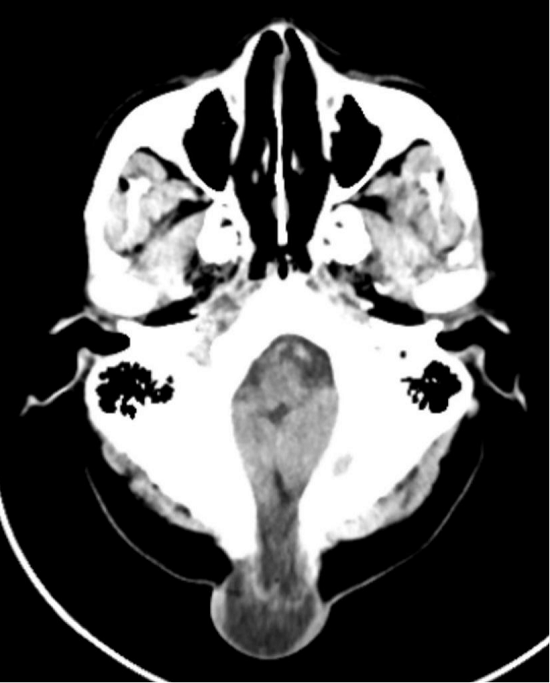

库女士自出生时,枕颈正中部位就有一个头皮肿物。幼时肿物体积不大,未进行诊治。随着年龄增长,这个肿物逐渐增大,且平躺、站立时,肿物的硬度和大小会发生明显变化。因担心这是先天性疾病,手术风险高,库女士和家人一直犹豫是否接受治疗,一拖就是45年。近期,肿物已增大至鸡蛋大小,且频繁出现枕颈部烧灼样疼痛,严重影响日常作息和生活质量,再也无法忍受的她,慕名来到平邑县人民医院神经外科一区就诊。经详细检查,库女士被确诊为“先天性脑膜脑膨出、先天性颅骨缺损”,并被收住入院。

先天性脑膜(脑)膨出是一种罕见的先天性神经管发育畸形,病因尚未完全明确,可能与胚胎时期神经管发育不良、中胚叶发育停滞有关,导致颅骨出现缺损,脑膜或脑膜脑组织经缺损区向外膨出。

✅ 临床表现:多在出生时或出生后数月、数年内发现头部囊性肿物,与头部相连,哭闹、咳嗽或用力时肿物会增大,局部可摸到骨缺损边缘。其中约75%发生在枕部,约12%发生在顶部偏中线等偏中线区域,肿物大小不一,内容物主要为脑膜、脑脊液,部分可包含脑组织。

✅ 诊断与治疗:颅脑MRI、CT及超声检查是诊断金标准,一旦发现异常,需及时到神经外科就诊。手术是根治性手段,不可按普通头皮肿物单纯切除(易损伤脑组织),核心是精细还纳或切除膨出物,严密修补硬脑膜和颅骨缺损,严防并发症。